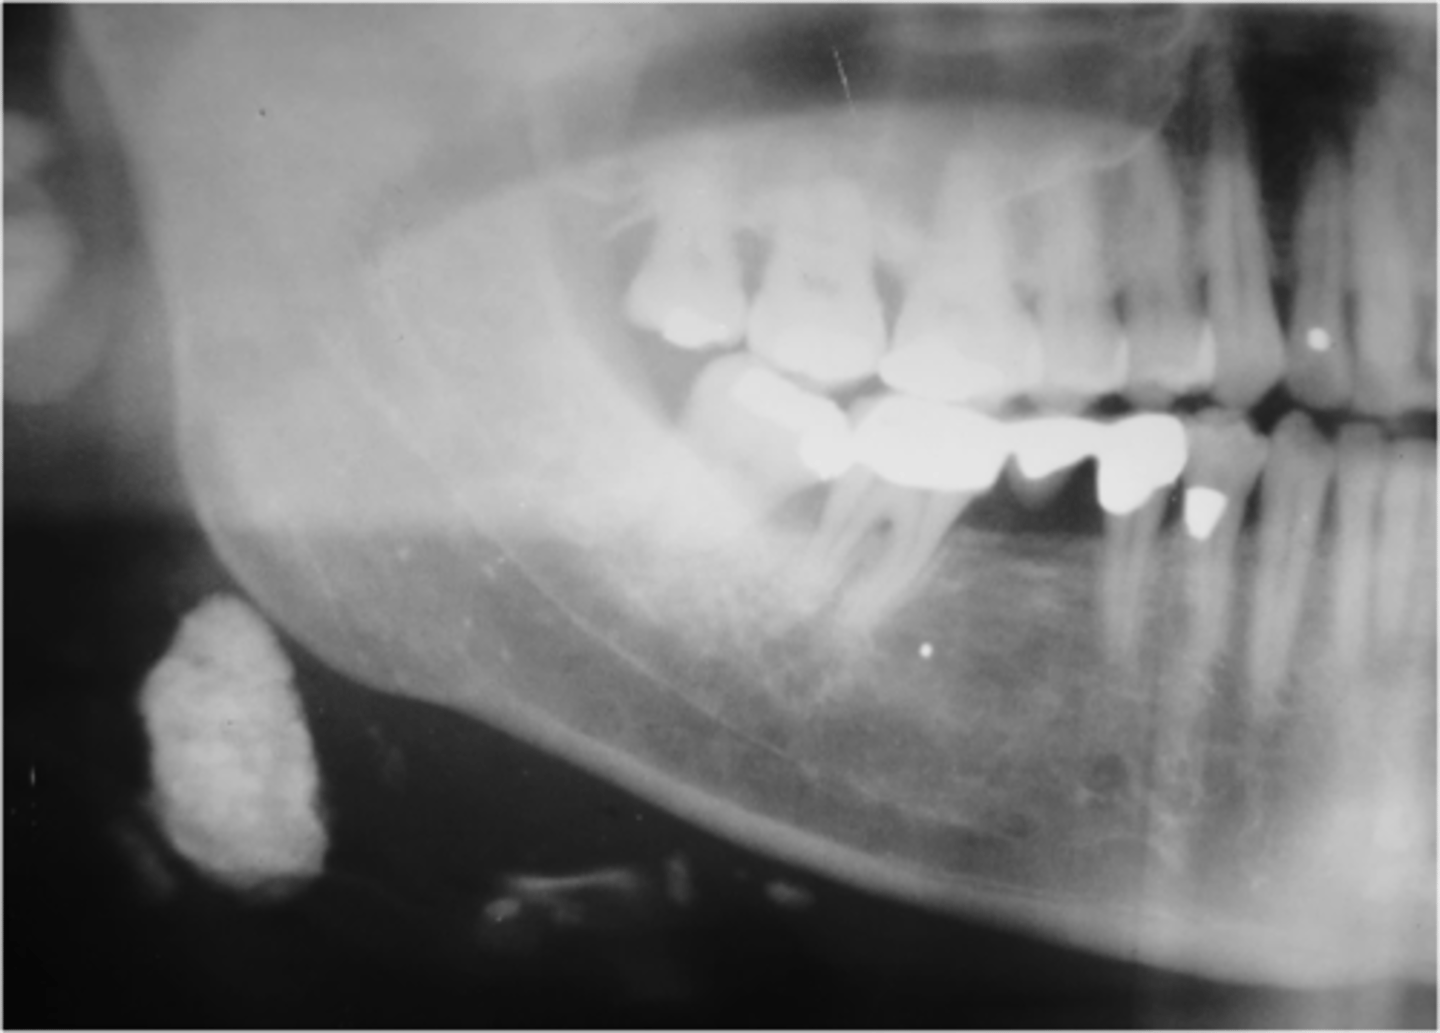

ID the pathology:

Swelling in wharton's duct

Sialolithiasis

ID the pathology during surgery:

Associated with pain upon salivation

What pathology is associated with pain upon salivation?

submandibular gland

80% of Sialolithiasis are associated with what gland?

Radiopaque mass

What is the radiographic features of a

Sialolithiasis?

ID the pathology based on the histology findings:

- Laminated calcified structure with central nidus

- Milking stone toward duct orifice